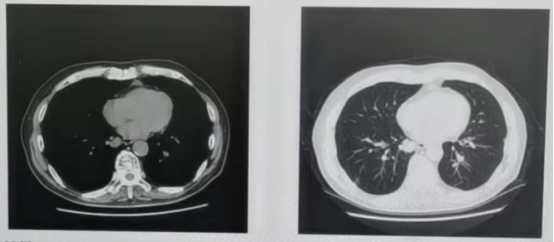

第四阶段治疗:2022年6月至2022年8月

因化疗耐受性较差,患者于2022年6月23日至2022年8月25日行贝伐珠单抗+卡培他滨治疗3周期。期间出现中度骨髓抑制,2022年7月23日血小板降至48*10^9/L。2022年7月复查胸部CT,提示双肺结节增大、增多(图8)。疗效评价:疾病进展(PD)。

图8 第4阶段双肺结节变化情况

第五阶段治疗:2022年8月至2023年1月

2022年8月,患者病情进展、骨髓抑制、自身无法耐受贝伐珠单抗+卡培他滨(PS评分:1分;升血小板治疗后血小板升至60-80*10^9/L),开启三线呋喹替尼单药治疗。

2023年1月复查胸部CT检查,提示双肺多个结节较前(2022年7月)增大,右侧肾上腺结节(图9)。疗效评价:PD。

图9 第五阶段双肺结节变化情况

第六阶段治疗:2023年2月至今

2023年2月至今接受呋喹替尼联合替雷利珠单抗治疗。2023年4月复查:疾病稳定(SD)。

2023年1月、4月复查胸部CT:肺部病灶部分缩小;上腹部MRI:肝V、VII段异常信号影(较大者大小2.5*1.6cm),较前变化不大,右侧肾上腺转移病灶增大(图11)。

图11 2023年1月、4月胸部CT及上腹部MRI